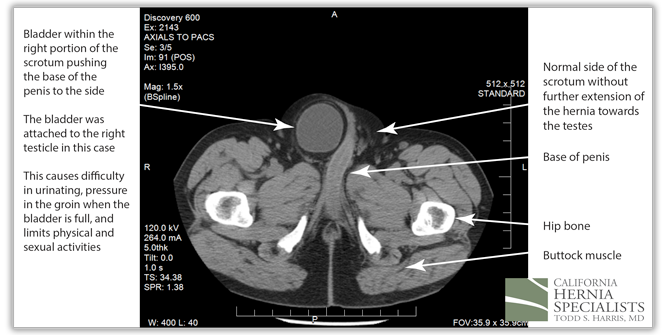

At the bottom of the hernia, the bladder on the right side was attached to the patients right testicle, and was pushing the base of the penis to the left side. When the patients bladder was full, he noticed severe pain in the groin, and difficulty urinating.

The patient underwent a laparoscopic bilateral inguinal hernia repair. During the surgery, the bladder was pulled out of the right groin hernia, and the fat was pulled out of the left hernia. Laparoscopic hernia mesh was placed to repair both groins. Due to the fact that the bladder was so close to the hernia repair, a bladder catheter was left in place for 2 weeks after the surgery to ensure complete healing.